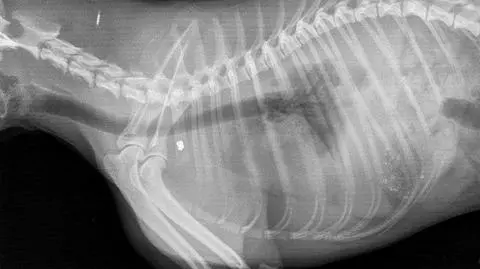

Kolejna ofiara wiatrówki. Wczoraj mówiliśmy o psie Pako, który został bestialsko zastrzelony, dziś powiemy o Preclu. To 2-letni kot, który kilka tygodni temu zginął w podobny sposób. Takich zwierząt jest znacznie więcej, bo skala znęcania się nad zwierzętami w naszym kraju rośnie. Pytanie, jak temu zapobiec i czy skutecznie ścigamy ich oprawców.